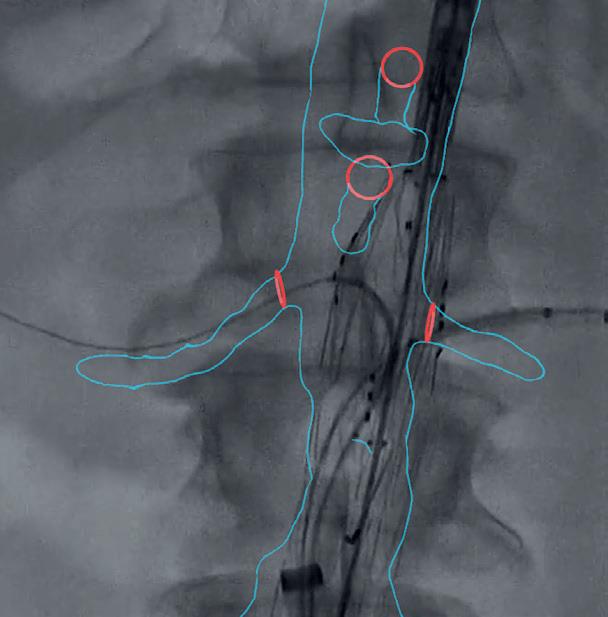

Surgical augmented intelligence: New evidence of radiation reduction benefit emerges

SURGICAL AUGMENTED intelligence in the form of 3D mapping during complex aortic procedures can decrease radiation exposure, fluoroscopy time and contrast use when combined with real-time fluoroscopic images, a new analysis has established

The results were presented during the 2022 Western Vascular Society (WVS) annual meeting in Victoria, Canada (Sept. 17–20) by Rohini Patel, MD, from the University of California San Diego. The researchers aimed to flesh out whether surgical augmented intelligence can be used to decrease radiation exposure in the operating room.

The retrospective chart review, from 2015–2021, looked at 116 patients who underwent a complex aortic repair— with 76 receiving a procedure using augmented intelligence. The majority underwent physician-modified endograft (PMEG) repair.

“Our group that was treated with augmented intelligence had almost half the amount of radiation exposure, with 1,955mGy compared to 3,755mGy in the non-augmented intelligence group,” Patel told WVS.

The former also saw a decrease in fluoroscopy time of around 56 minutes compared to 87 minutes in the latter group of patients, with contrast use significantly decreased to 122cc from 199cc, she added.

Adjusted analysis showed these significant reductions remained, Patel explained.

“Overall, we believe that surgical augmented intelligence is a way to decrease radiation exposure for the entire team and should be further investigated,” she said.—Bryan Kay

3D mapping during an aortic procedure